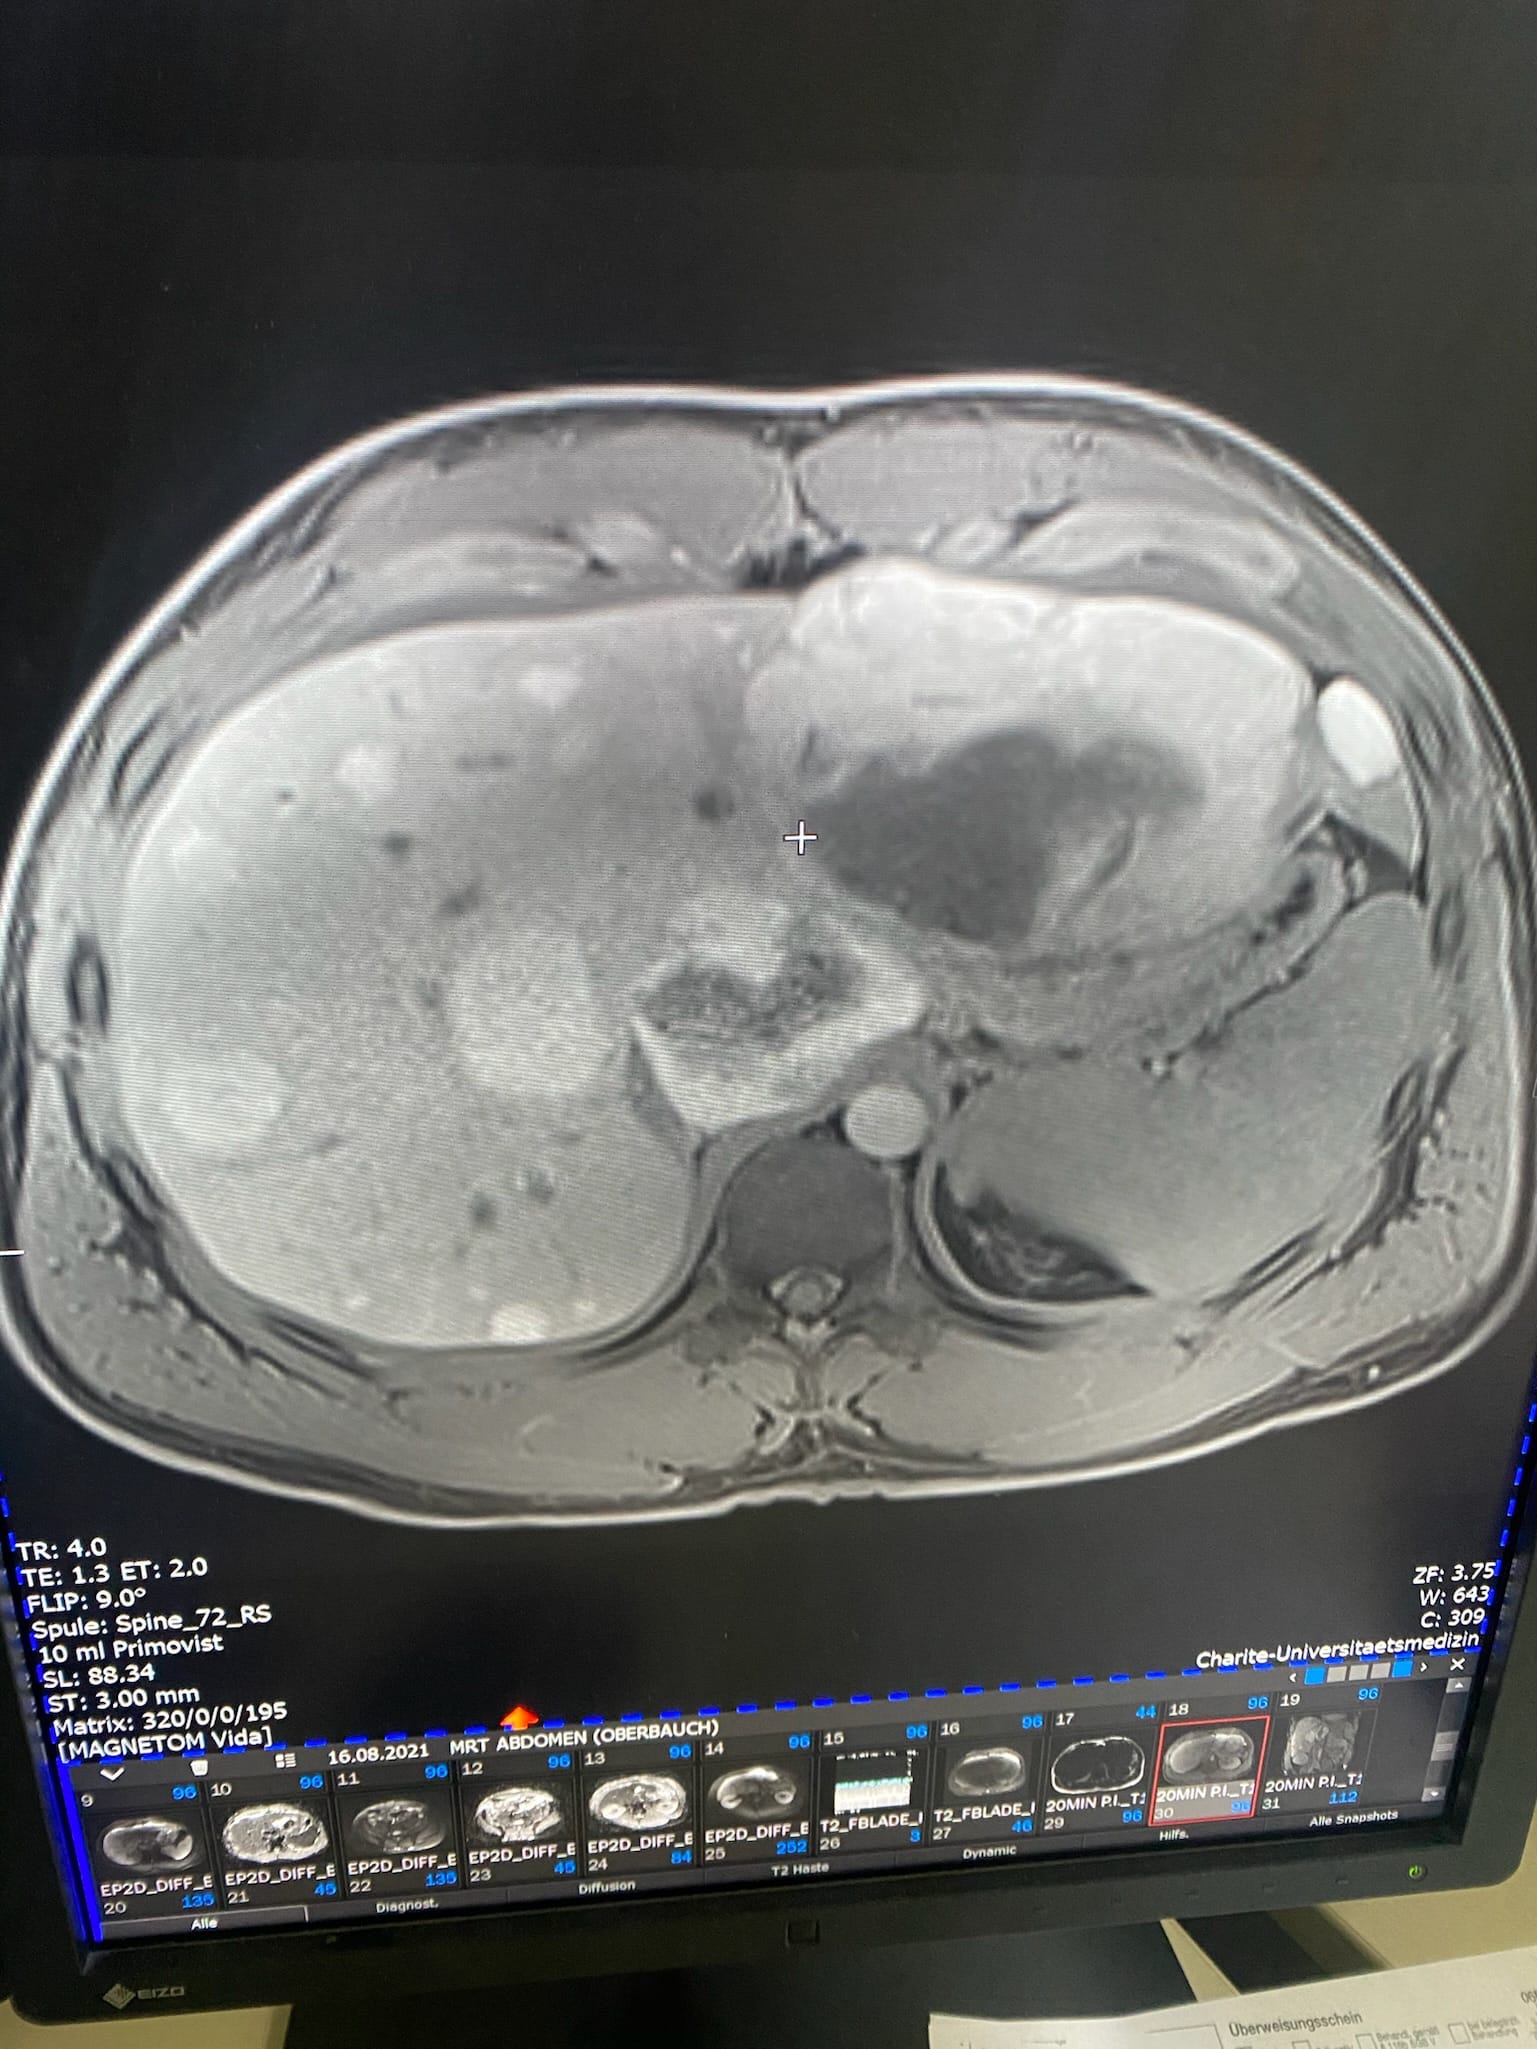

2021 erhielt ich die Diagnose: Leberkrebs HCC. Palliativpatient. Mehr als 10 Tumore, der größte 13,8cm. Die Ärzte gaben mir ein halbes Jahr. Heute bin ich hier – stärker als je zuvor.